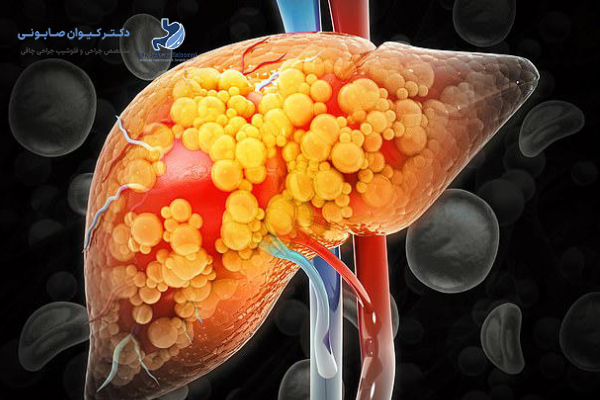

کبد چرب غیرالکلی (NAFLD) به شرایطی گفته میشود که در آن بیش از 5 تا 10 درصد وزن کبد از چربی تشکیل شده باشد. علت اصلی آن اغلب سبک زندگی ناسالم، پرخوری، مصرف غذاهای پرچرب و قند بالا، همراه با کم تحرکی است.

عوامل خطر اصلی شامل چاقی، دیابت نوع 2، فشار خون بالا و کلسترول بالا هستند. این بیماری به تدریج پیشرفت میکند و در صورت عدم درمان، احتمال بروز عوارض جدی کبدی وجود دارد.

چاقی به عنوان مهمترین عامل ابتلا به کبد چرب شناخته میشود. در افراد دارای شاخص توده بدنی بالا (BMI>30)، احتمال تجمع چربی در کبد بسیار بیشتر است. سلول های چربی اضافی نه تنها در زیر پوست، بلکه در اطراف اندام های داخلی از جمله کبد رسوب میکنند. این تجمع چربی، مقاومت به انسولین را افزایش داده و سبب اختلال در متابولیسم قند و چربی میشود.